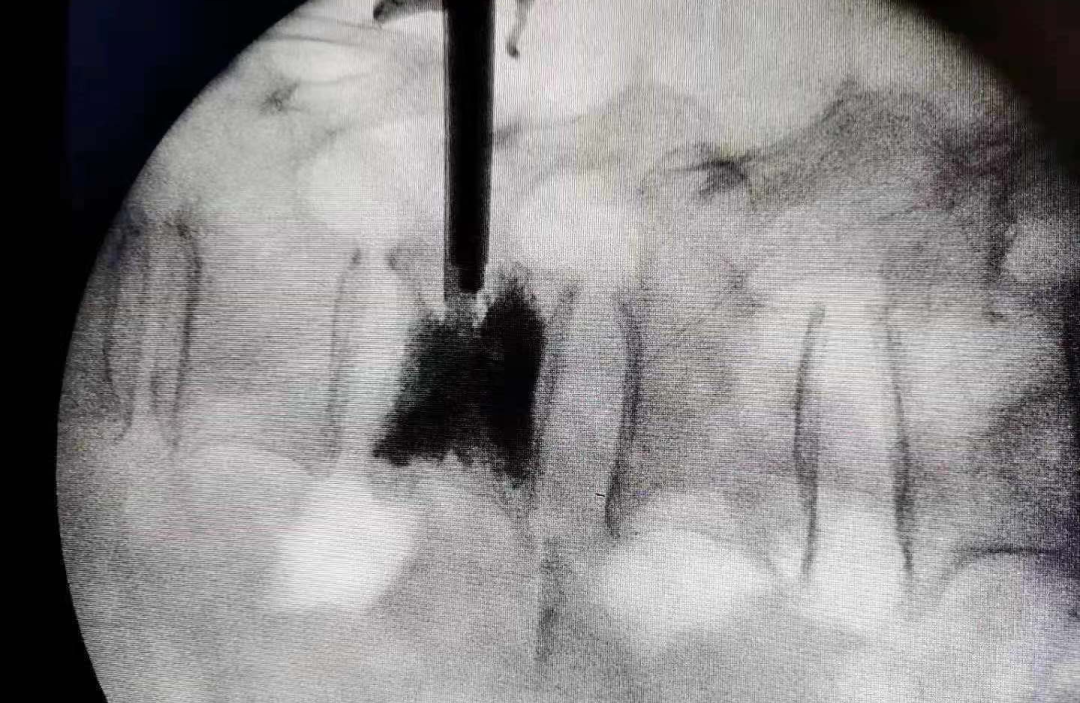

A1:很有可能胸腰椎骨折!隨著年齡增大,人體的鈣流失加快,極有可能會導致骨質疏松。嚴重的骨質疏松,即使打個噴嚏,抖一下被子,都會導致胸腰椎的骨折。如果有躺著或站著不動,腰背部疼痛不明顯,稍微動一動,疼痛明顯,起床或者躺下的過程更難受的情況出現(xiàn),應該引起重視,及時去醫(yī)院拍X片或做磁共振,確定是否有骨折現(xiàn)象的存在,若不及時處理,很有可能會逐漸駝背。針對老年人骨質疏松癥導致的胸腰椎骨折,建議行微創(chuàng)骨水泥成形術,成功率高,手術風險小。徐榮敏醫(yī)生做過的手術中,患者年齡最大的有103歲。術后2年,老人狀態(tài)良好,家人都說多虧現(xiàn)代醫(yī)療技術的進步。